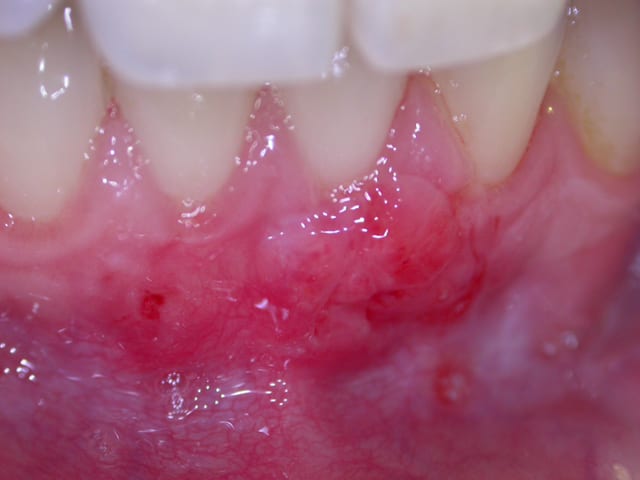

comme evoqué avec l'amibe....voila ce cas d'une jeune patiente sur qui j'ai fais une greffe conjonctive il y a 1 an et qui vient en contrôle .....le contrôle de plaque n'est parfait mais j'ai fait ouvrir et pris la photo comme ca .....

ce qui me pose question c'est que ce qui recouvre les racines en vestibulaire est dur .....y a t il de l'os et si oui quel type d'attache en dessous .....ankylose , os + EJL, os + attachement conjonctif ou Neoattache ?.....en tout cas l'amibe il n'y a pas de poche vestibulaire !!

Ce que tu disais a propos de l'impossibilité d'avoir de l'os .....c'est bien mon problème .....je ne comprends pas !!!et il m'est arrivé d'avoir des exostoses quasiment .....c'est pas beau et genant.....

Oui j'ai lu pas mal de trucs sur ces techniques ......mais ce qui m'étonne c'est ce tissu dur en vestibulaire .......a un endroit ou logiquement devrait pas y en avoir ....

....ce cas n'as qu'un an de recul mais peut être que dans 1 an il y aura un tissu bp plus epais ( une voussure ).....j'ai au moins un cas en tête ou il y avait une veritable exostose après obligeant à retoucher......( je n'ai maleureusement pas documenté le cas )